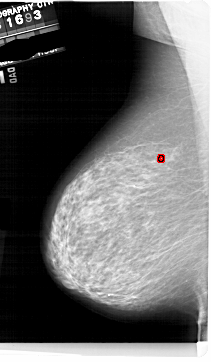

A_1854_1.LEFT_MLO

LEFT_MLO LINES 6871 PIXELS_PER_LINE 4006 BITS_PER_PIXEL 12 RESOLUTION 43.5 OVERLAY

FILE: A_1854_1.LEFT_MLO.OVERLAY

TOTAL_ABNORMALITIES 1

ABNORMALITY 1

LESION_TYPE CALCIFICATION TYPE PLEOMORPHIC DISTRIBUTION CLUSTERED

ASSESSMENT 4

SUBTLETY 2

PATHOLOGY BENIGN

TOTAL_OUTLINES 1

BOUNDARY